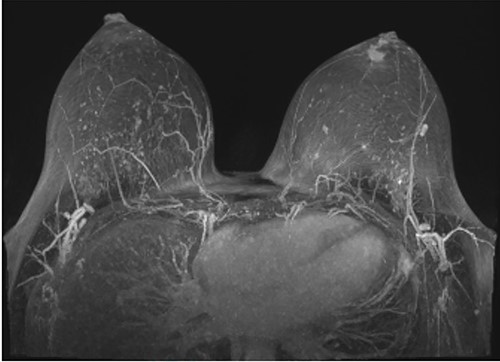

Following initial review, the patient was referred for a magnetic resonance image (MRI) which demonstrated an indeterminate retro-areolar lesion in the left breast (Fig. 2). A targeted ultrasound and core needle biopsy also showed active chronic periductal, interlobular and interstitial inflammation with focal duct ectasia consistent with Breast Imaging Reporting and Database System (BI-RADS) score of 2. Histological analysis showed predominant eosinophilic infiltrate (Fig. 3). There was no evidence of granulomatous inflammation or malignancy and staining for fungal elements and mycobacterium was also negative. A biopsy of the adjacent skin showed ongoing periductal and interstitial chronic inflammatory cell infiltrate with focal abscess formation (Fig. 4).

Histology of the surrounding breast tissue adjacent to the left retro-areolar complex.